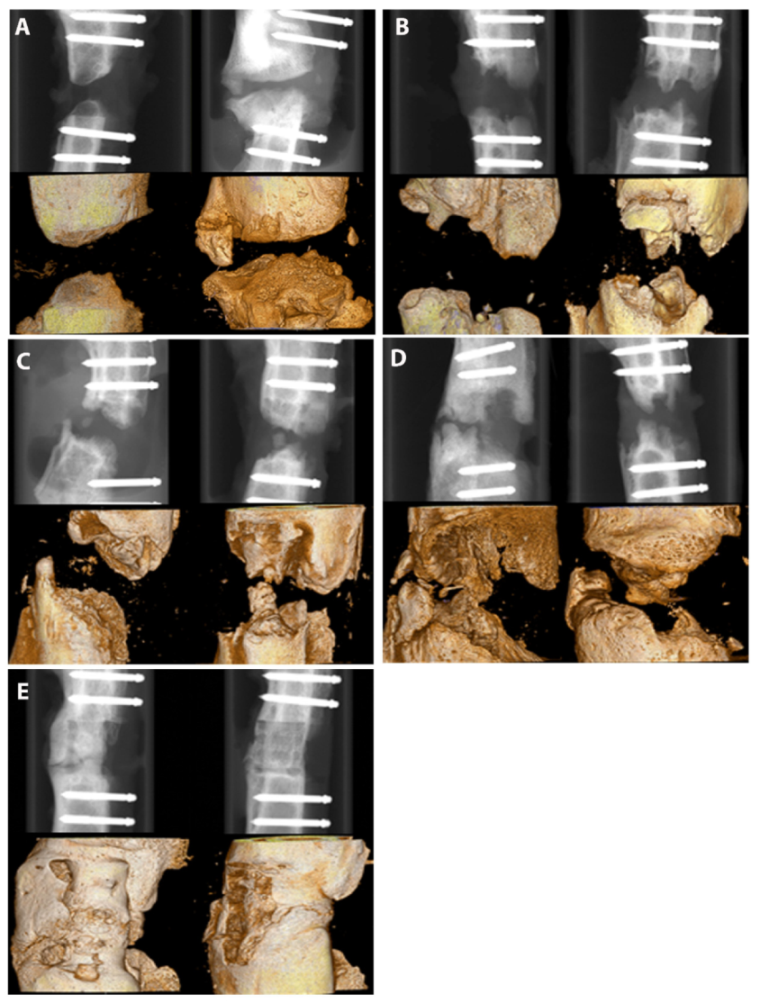

2.2. Course of Bone Regeneration

3.4. µCT Analyses/Bone Volume/Total Volume